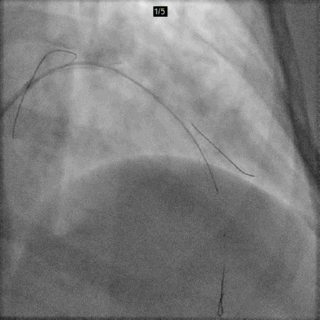

Cx Wire (Anchor)

以CAU体位的造影静态图为路标,送入回旋支导丝

LAD Wire

先后以CAU及CRA体位的造影静态图为路标,送入前降支导丝

D1 Wire

以CRA体位的造影静态图为路标,送入对角支导丝